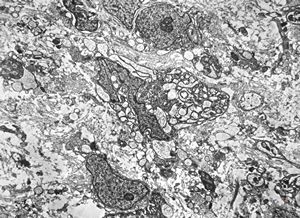

F,25y. | myopathy - atrophic and regenerating muscle cells